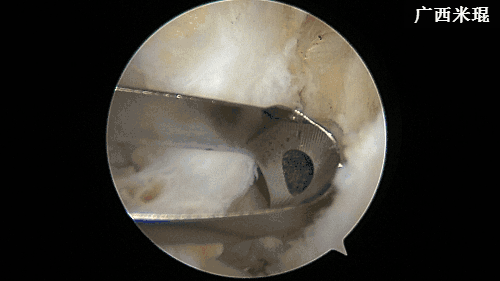

(七)清理髁间窝

维持膝关节屈曲90度,关节镜监视下建立偏高位的前内入路,置入关节镜刨刀及等离子刀,清除髁间窝滑膜、ACL残端,显露髁间窝外侧壁的后方,用等离子刀标注ACL胫骨隧道及股骨隧道内口。然后在关节镜监视下建立前内入路内下方的辅助入路。此操作2分钟内完成。